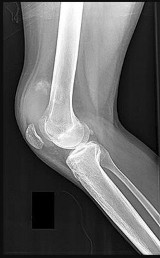

A 15-year-old boy presents with a permeative lytic lesion in the femoral diaphysis with aggressive periosteal reaction ('onion skinning'). Biopsy reveals uniform small round blue cells. Cytogenetic analysis of this tumor will most likely demonstrate which of the following translocations?

Correct Answer: t(11;22)

Explanation:

The clinical and radiographic description is classic for Ewing sarcoma. The characteristic cytogenetic abnormality is a balanced translocation t(11;22)(q24;q12), which fuses the EWS gene on chromosome 22 with the FLI1 gene on chromosome 11. This is seen in approximately 85-90% of Ewing sarcomas. t(9;22) is the Philadelphia chromosome (CML), t(X;18) is seen in synovial sarcoma, t(2;13) in alveolar rhabdomyosarcoma, and t(12;16) in myxoid liposarcoma.